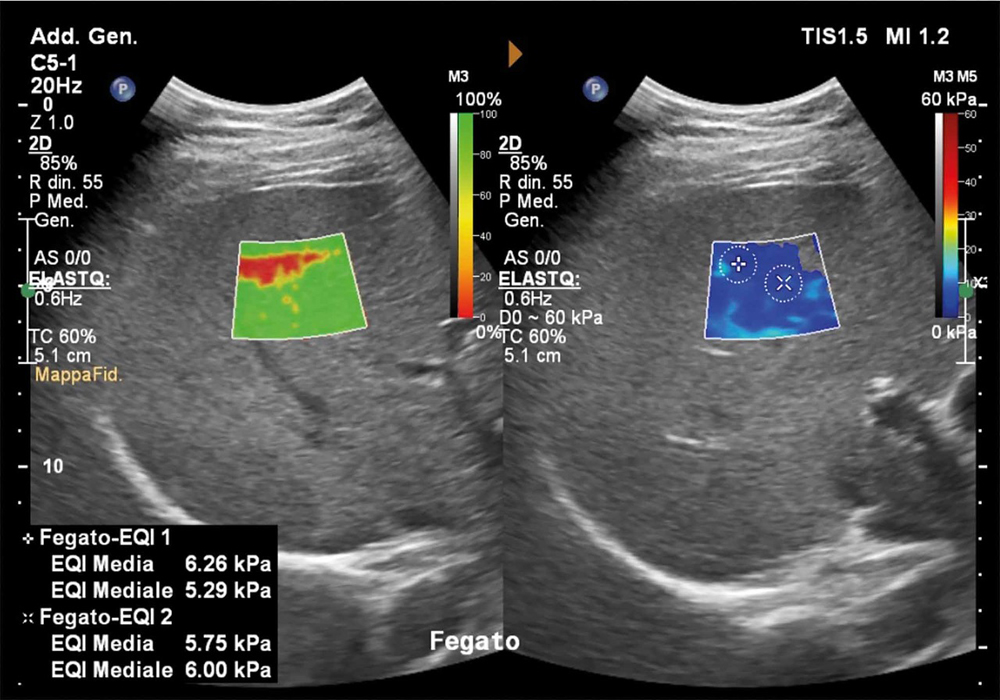

Una delle applicazioni più importanti è la valutazione della fibrosi epatica. Il fegato, in presenza di infiammazioni croniche come le epatiti virali e di steatosi, può sviluppare fibrosi, cioè una sostituzione del tessuto sano con tessuto cicatriziale più rigido. «L’elastosonografia shear wave ci consente di stimare la rigidità del fegato senza ricorrere alla biopsia epatica — spiega il dott. Ivona — offrendo una stima affidabile e ripetibile nel tempo». Questo permette di monitorare l’evoluzione della malattia, valutare l’efficacia delle terapie e individuare precocemente i pazienti a rischio di cirrosi, riducendo l’uso di procedure invasive. L’esame è indicato per chi soffre di epatite cronica B o C, steatosi epatica, epatopatie alcoliche o patologie autoimmuni del fegato.